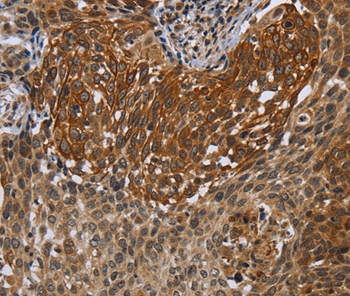

Immunohistochemical analysis of paraffin-embedded Human cervical cancer tissue using #37761 at dilution 1/40.

Immunohistochemical analysis of paraffin-embedded Human thyroid cancer tissue using #37761 at dilution 1/40.